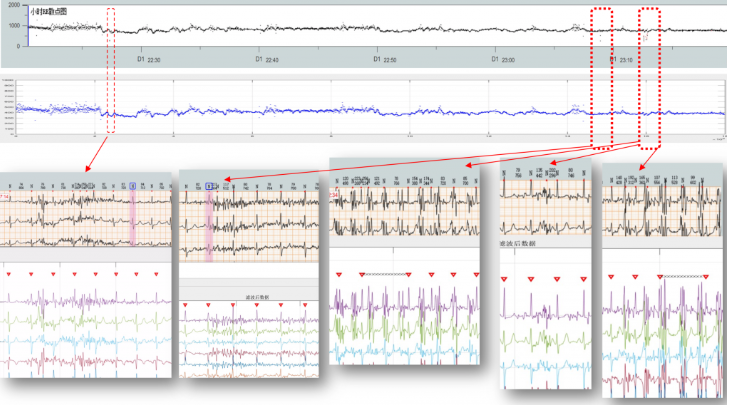

医疗滤波器性能展示

R峰识别准确率展示